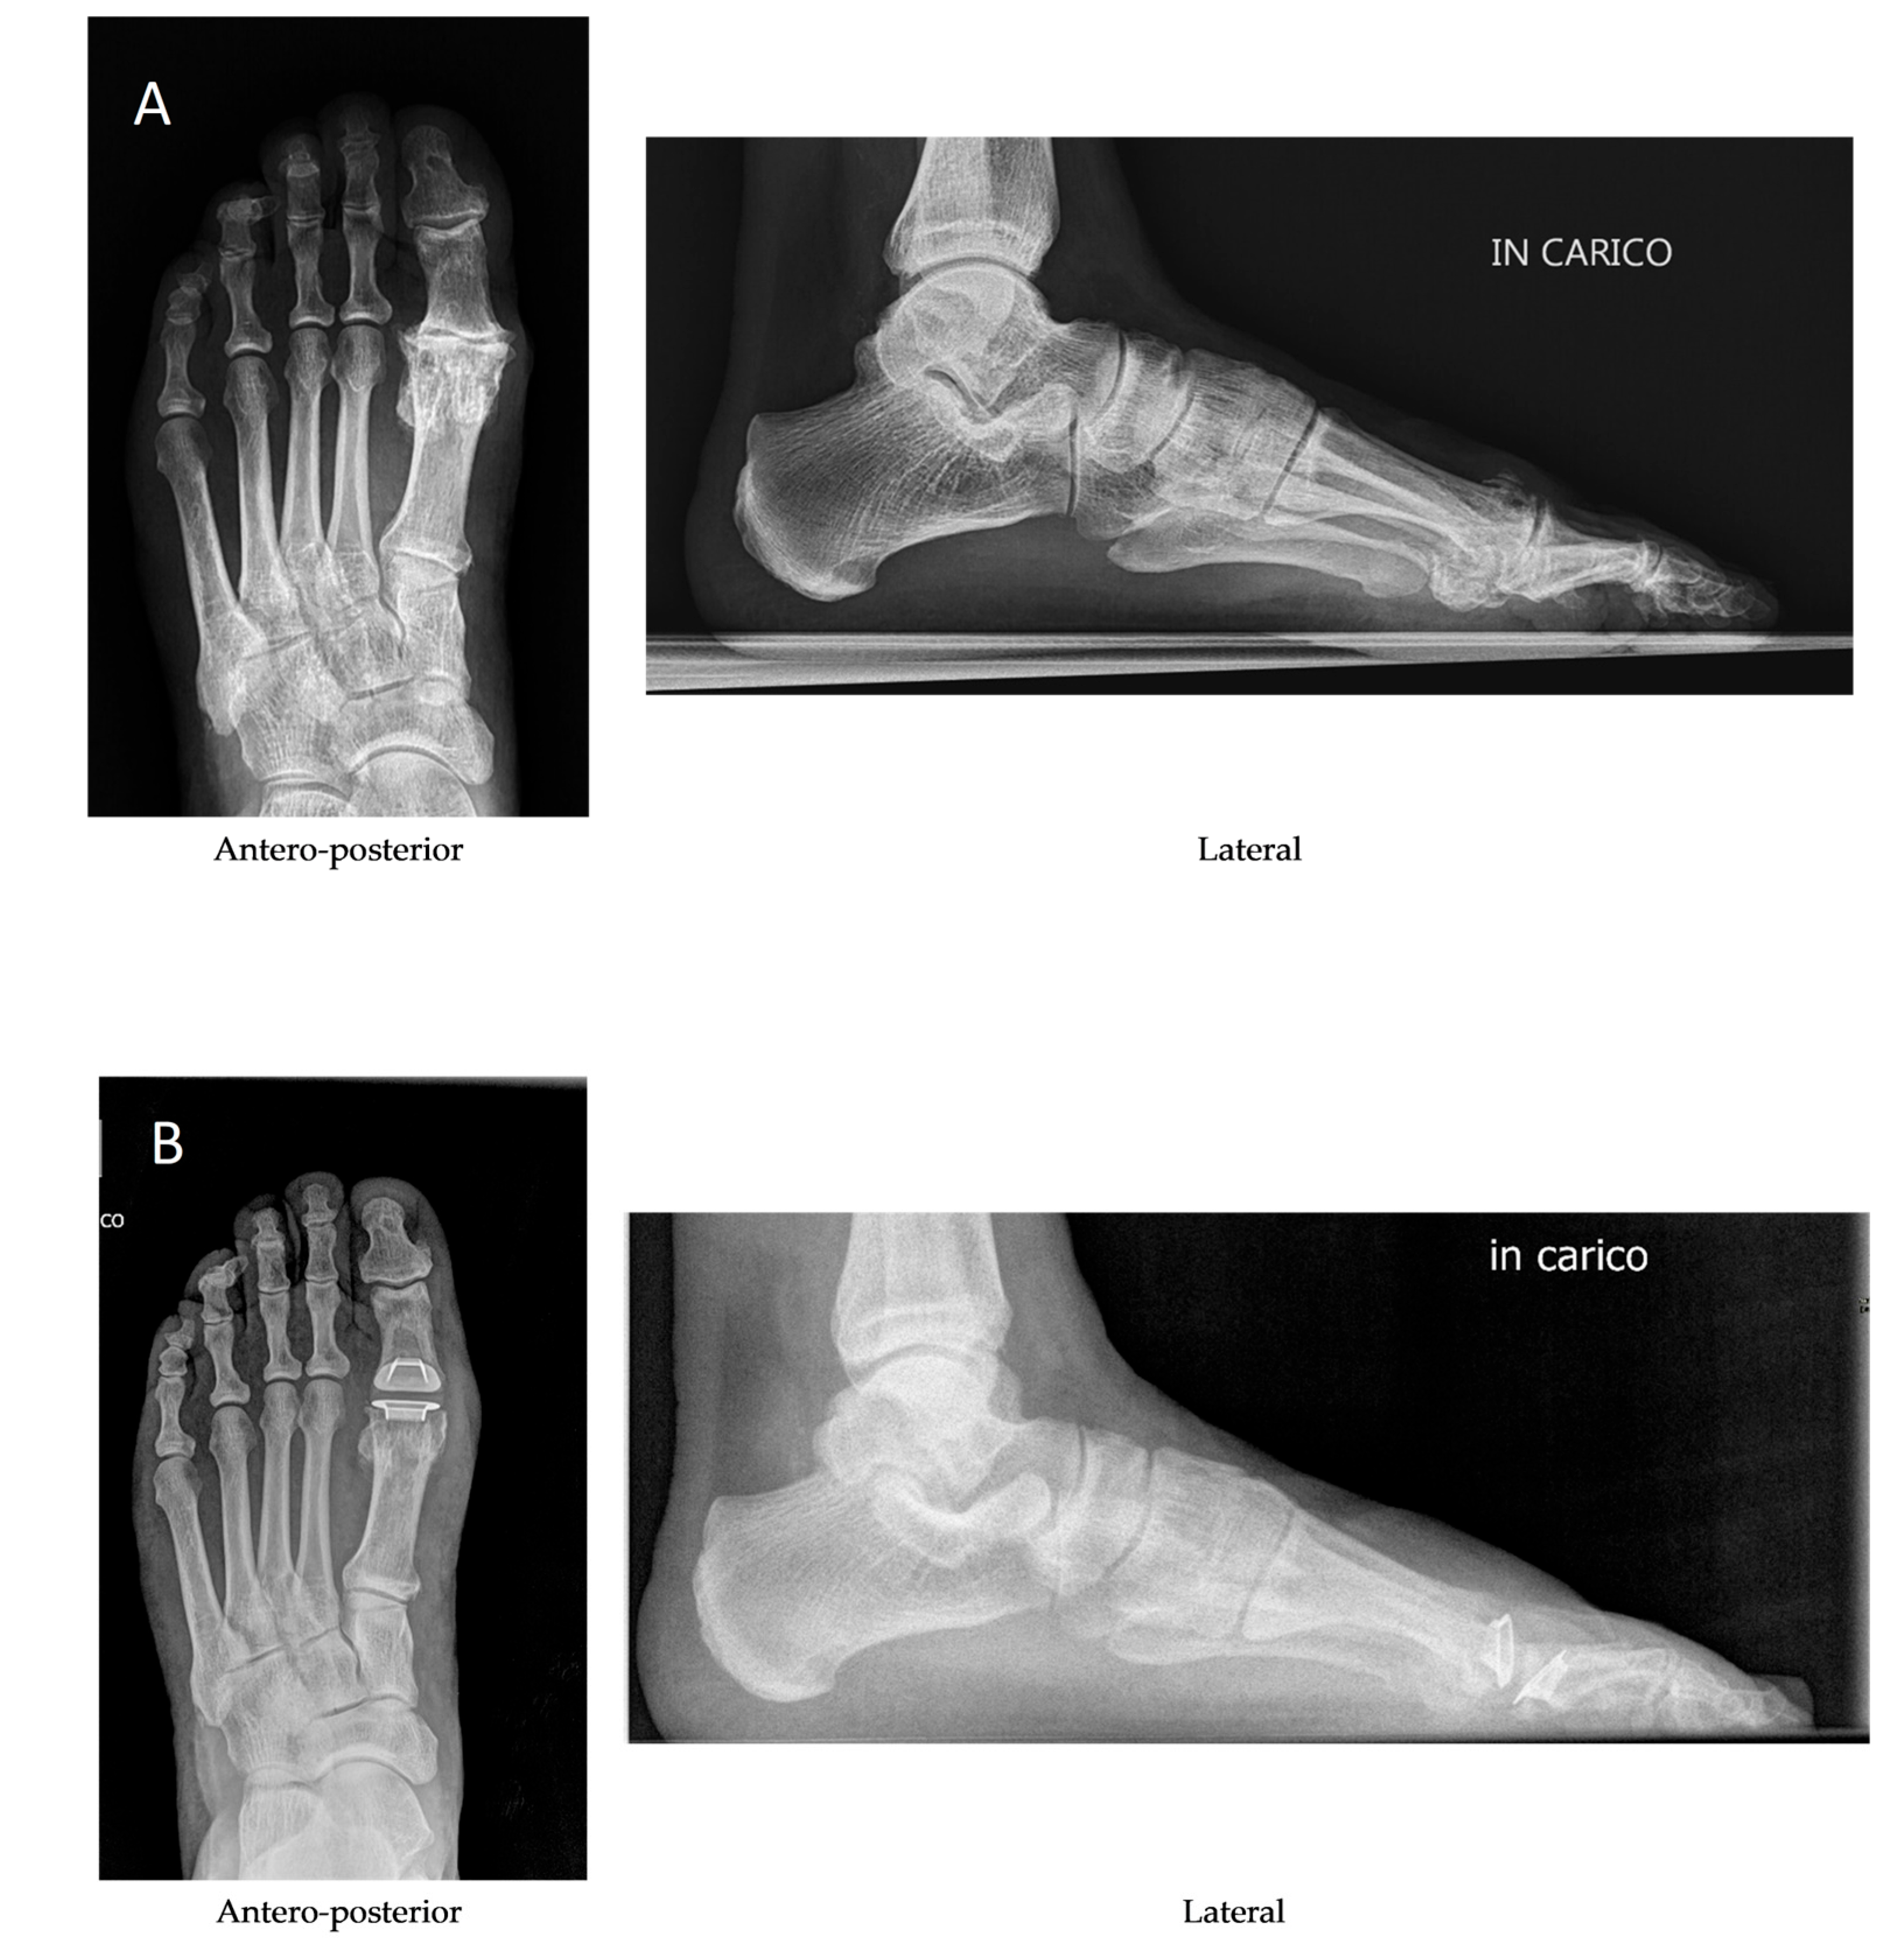

1. Introduction

2. Materials and Methods

2.2. Operative Technique, Postoperative Care and Follow-Up

- The sagittal angulation of the metatarsal and phalangeal stems reproduces the alignment of the toe in a neutral position and therefore maintains natural muscle and tendon tensions at rest and while walking.